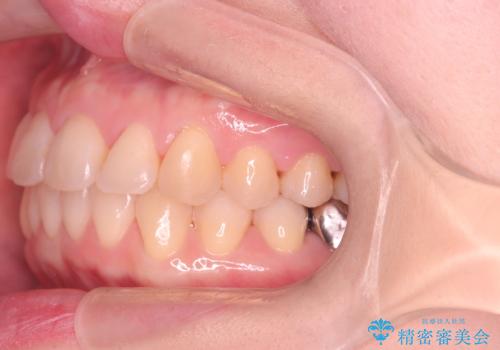

- 前歯の翼状捻転の改善を希望してこられた患者様です。

下顎の叢生はインビザラインで解決することがきましたが、上顎の捻転が完全には改善できなかったため、上顎は途中からワイヤーを用いて治療を行っています。

捻転の改善はインビザラインで苦手とするところですので、うまく治らない場合はワイヤーを提案しています。